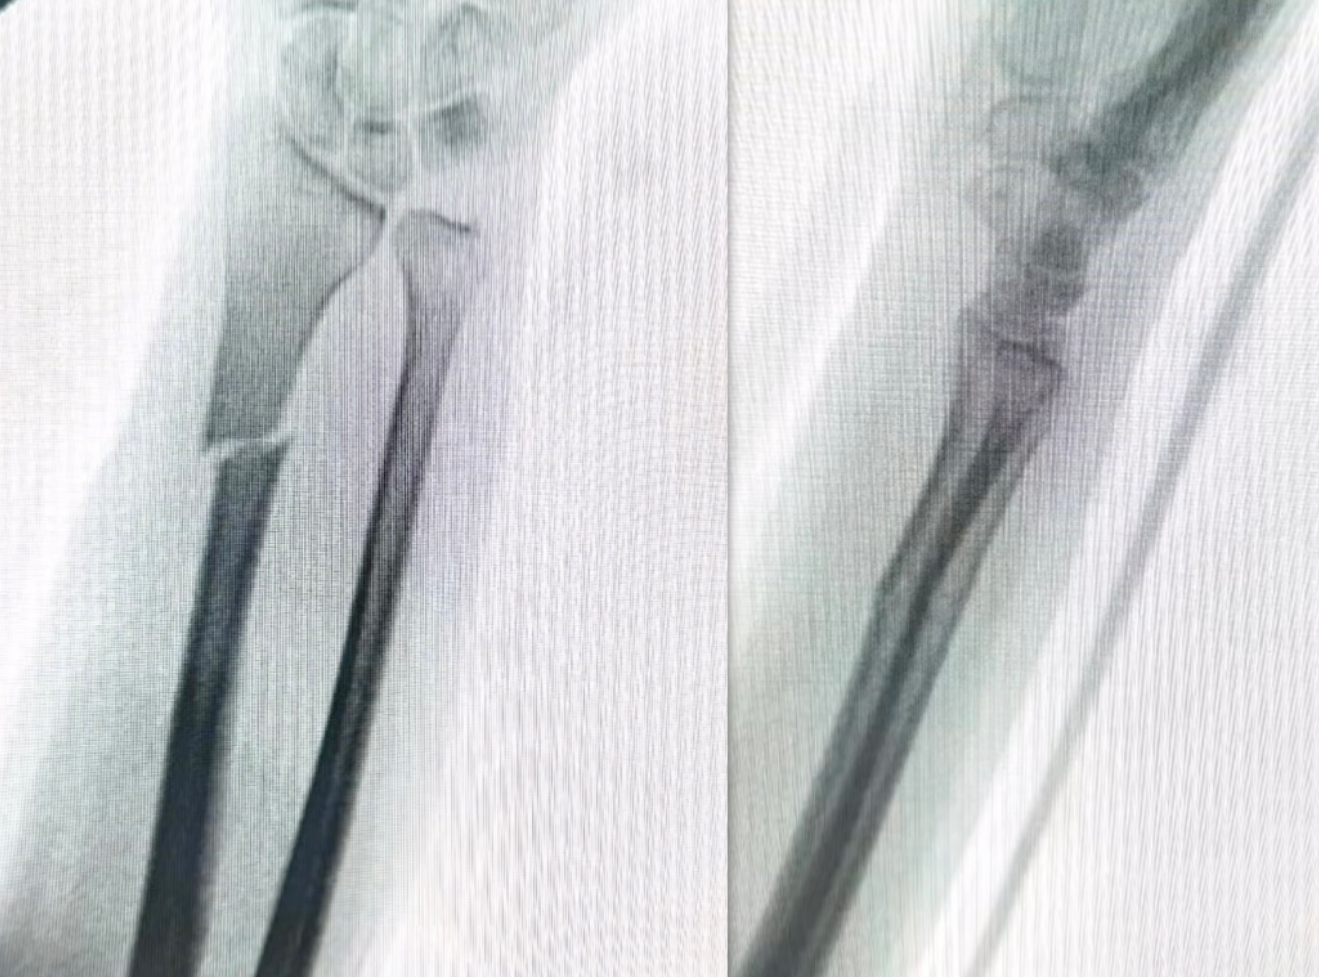

蓋氏骨折復(fù)位前 蓋氏骨折復(fù)位后